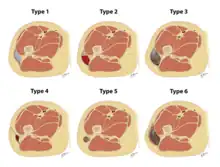

The Mellado-Bencardino classification can be used to describe a Morel-Lavallée lesion based on its MRI.[5] The classification categorizes the lesions into types.[8] The classification has six stages listed as Type I to Type VI.[5] The types do not align with specific treatments or outcomes.[4][8] The stages are based on multiple factors that can be observed on the lesion's MRI.[5] These factors include the following: the shape of the lesion, specific MRI features, and whether a capsule is present.[5][8]